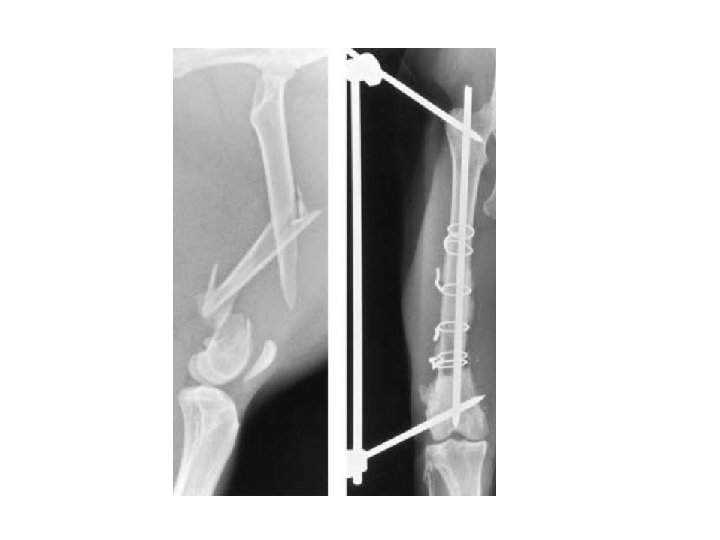

Bekkenkanteling: bekken wordt op meerdere plaatsen gebroken

HD therapie • Geringe HD, weinig last: bewegingsschema (zwemmen!) + normaal gewicht • Middelmatige HD: pijnstiller en ontstekingsremmer + fysio • Ernstige HD: Bekkenkanteling (jong dier), myotomie of heupkopresectie (oudere dieren) https: //www. youtube. com/watch? v=j. YQmet. ZYmo